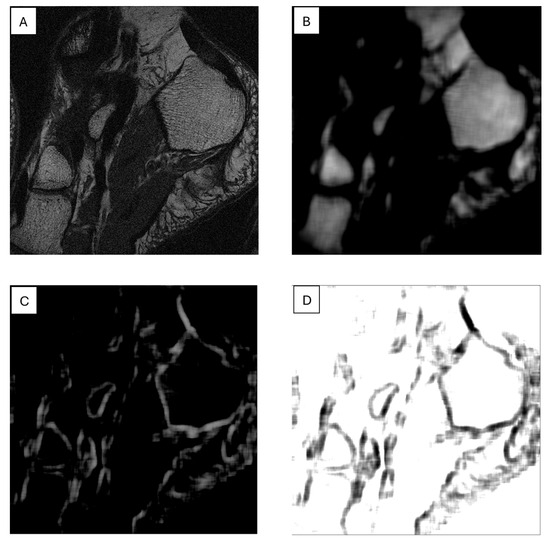

Another example of using such maps for image segmentation is shown in Figure 5, determined for the SumAverage parameter from GLCM for a 15 × 15-pixel sliding window across the T1W MR image of a foot cross-section; bone regions are shown on this map as smooth areas with a small range of brightness levels, which allows them to be relatively easily distinguished from other regions. Texture feature maps can also be used for edge detection. Figure 5C,D shows such maps, obtained for the SumOfSquares (GLM) and Sigma (autoregressive model) features, respectively, in which the edges shown define bone tissue regions. An example of a texture map application combined with an active contour model for biomedical image segmentation is discussed in reference [105].

Figure 5.

T1W MR image of the foot bone (A); feature maps calculated for this image: SumAverage (B); SumOfSquares (C); and Sigma (D).